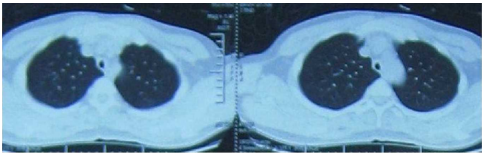

• 胸部CT:可发现气管和支气管树的狭窄程度及范围,气管和支气管壁增厚钙化、管腔狭窄变形及肿大的纵隔淋巴结;呼气末CT扫描可观察气道的塌陷程度。

图片